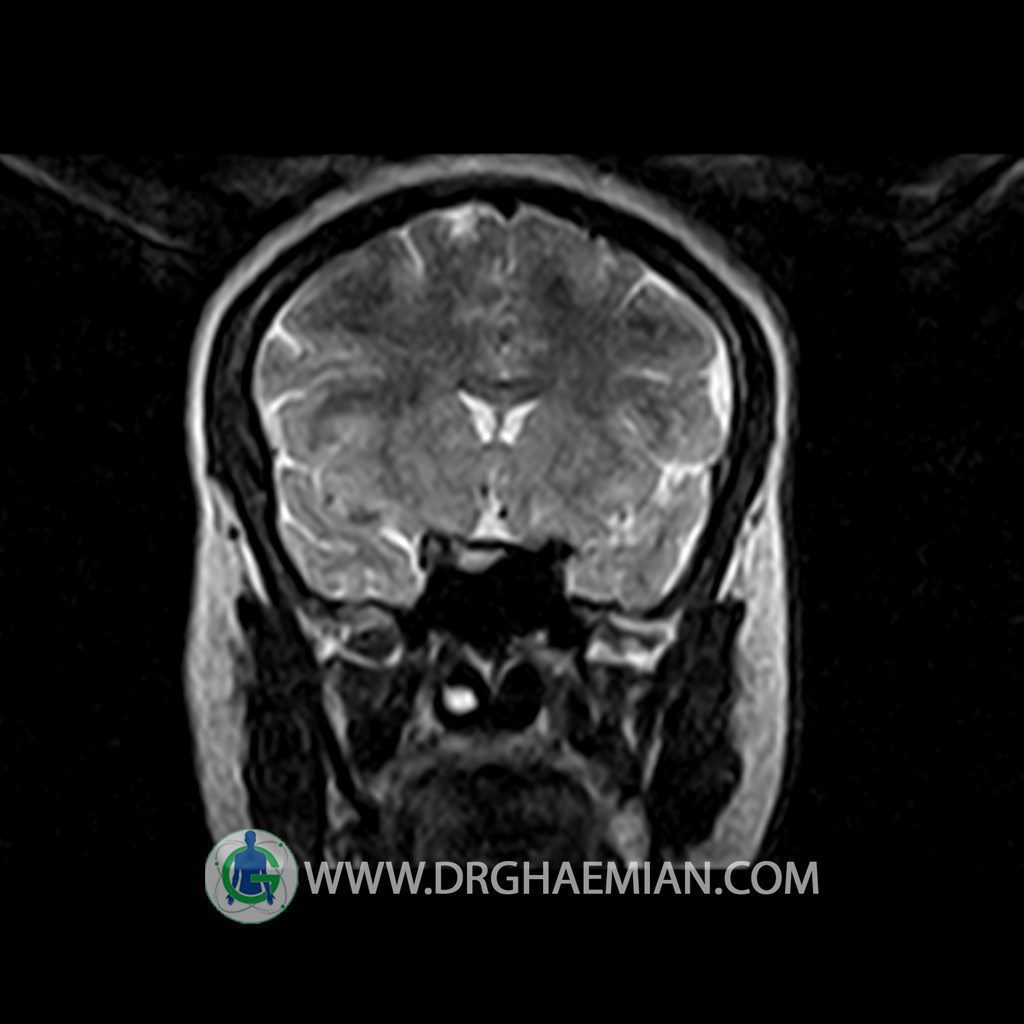

ام آر آی هیپوفیز یک روش تصویر برداری است که از غده هیپوفیز (غده ایی کوچک در مغز که هرومون ها و دیگر غدد بدن را کنترل می کند) و ناحیه های پیرامونش در مغز تصاویری ایجاد می کند. در این کیس سلای نسبتا خالی در ناحیه هیپوفیز بیمار مشاهده می شود.

Technique: Axial , coronal T1 , Axial , coronal , sagittal T2 , Axial, coronal T1 post Gd & 64 dynamic thin coronal slices.

– Extension of suprasella cistern to sella with thin pituitary gland in floor of sella ( partial empty sella )

is seen